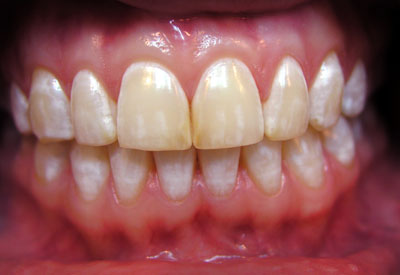

Фото эрозивной, эндемической, штриховой формы

Фото 2. Эндемическая форма флюороза, равивается по причине повышенного содержания фтора в питьевой воде.